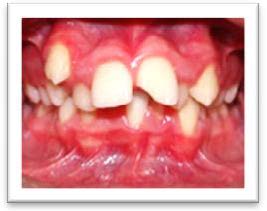

Raisons esthétiques

Malpositions dentaires, dissymétries faciales majeures.